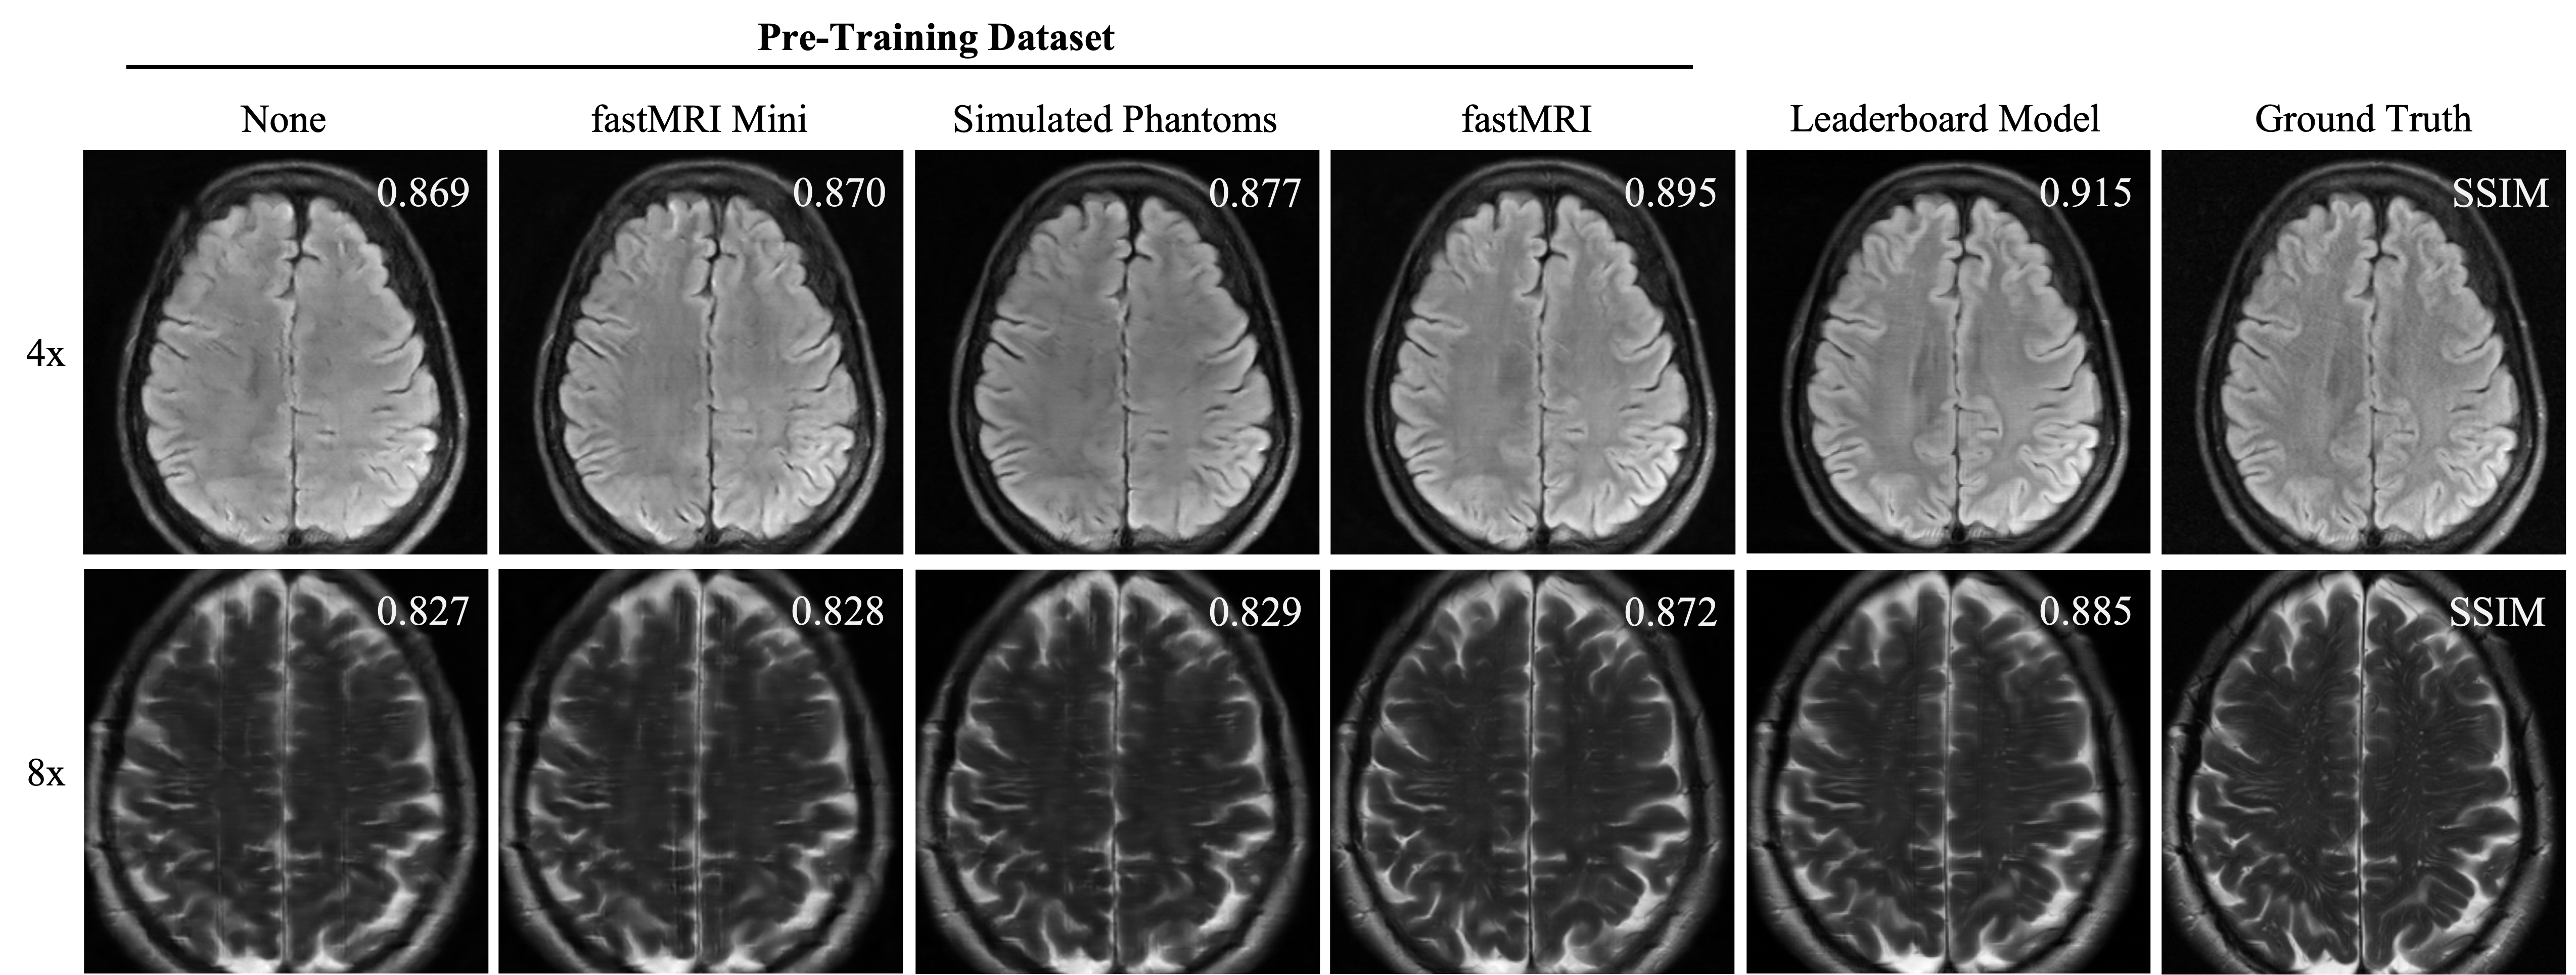

table:transferlearning Pre-Training Fine-Tuning SSIM () NMSE () PSNR — fastMRI Mini fastMRI Mini fastMRI Mini Simulated Phantoms fastMRI Mini fastMRI fastMRI Mini Full fastMRI dataset for 50 epochs

4.4 Phantom Pre-Training

Pre-training an E2E-VarNet reconstructor using a simulated Shepp-Logan phantoms improves model performance in reconstructing clinically acquired brain images when compared to working solely with a restricted dataset, based on both quantitative (\tablereftable:transferlearning, \figurereffig:tl) and qualitative (\sectionrefsection:tl-supp) results. Of note, pre-training took less than a day and fine-tuning under 3 hours using a single 16 GB Tesla P100 GPU. These metrics allow for rapid, inexpensive model iteration and experimentation before final benchmarking on a more sophisticated compute cluster.

A.4 Phantom Pre-Training

For our transfer learning experiments, all input signal data for model training and testing was fixed at 4x and 8x acceleration factors. We tested our model on the fastMRI multi-coil validation dataset partition, excluding the volumes that were used in the fastMRI Mini dataset for fine-tuning.

B.4 Phantom Pre-Training

fig:tl includes a sample panel of image reconstructions on the final test dataset after model training. Qualitatively, we found that phantom-based pre-training allowed the model to generalize better to previously unseen contexts, such as through reduction of image feature blurring and tissue texture contrast when compared to training on the fastMRI Mini dataset alone (\figurereffig:tl). \figurereffig:tl-histogram shows a panel of histograms of pair-wise SSIM improvements comparing a reconstructor model pre-trained on simulated phantom data and one pre-trained on the fastMRI Mini dataset.